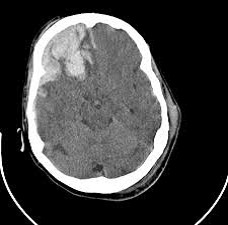

(SES-PE 2018 ACESSO DIRETO) - Homem, 27anos envolvido em acidente motociclístico em alta velocidade (colisão). Admitido na emergência terciária com 9 pontos na escala de Glasgow, realizou a imagem abaixo. Qual o diagnóstico provável?

A) Concussão clássica

B) Concussão simples

C) Lesão axonal difusa

D) Contusão cerebral

E) Hematoma subdural

Letra “D” - Contusão cerebral

CONCUSSÃO: PERDA DA CONSCIÊNCIA <6H